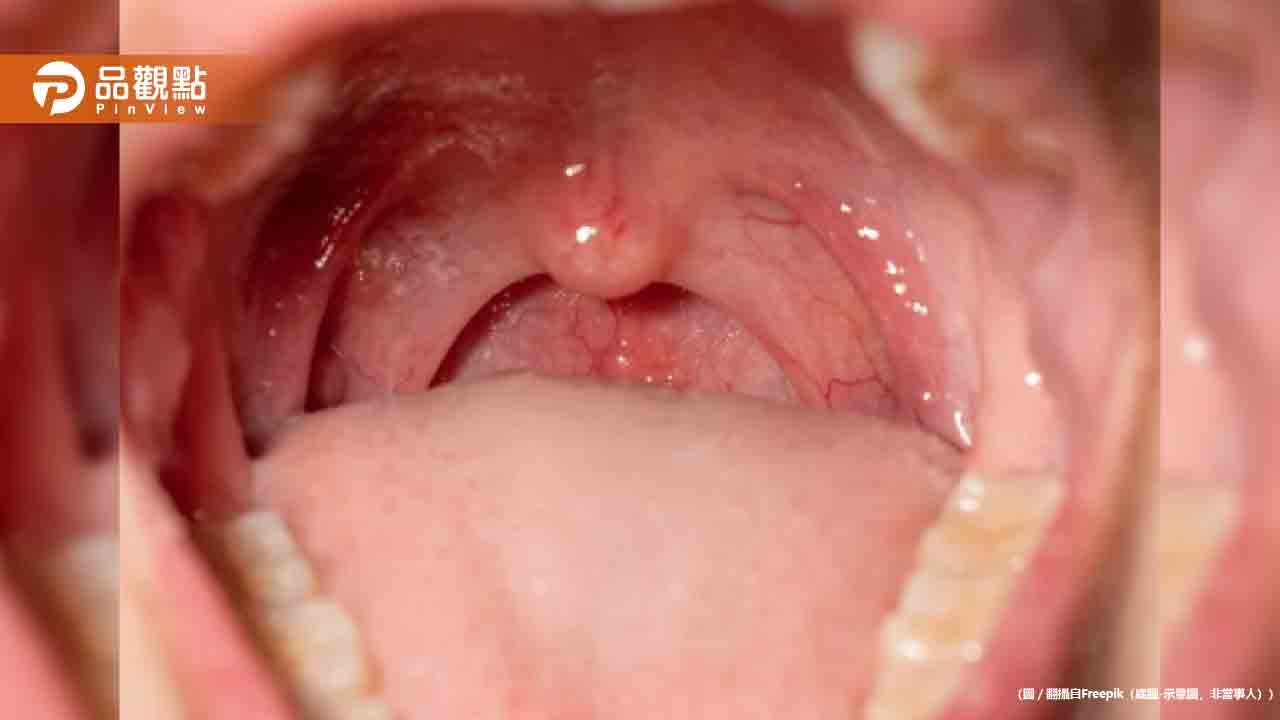

口腔癌為台灣男性惡性腫瘤發生率第四位,每年新增8000人,5年存活率不到3成。現行公費口腔癌篩檢是十大癌症中唯一採用目視進行初步判斷的癌種,且每2年進行一次,難以及時發現病灶。

台大醫學院放射線科主任陳世杰表示,口腔癌患者警覺性不高、診斷頻率不夠及時、具專科診斷能力的口腔外科醫師不多,導致患者發現時多已晚期。因此台大整合醫學影像、口腔醫學、生醫工程與AI專家,開發此套快篩系統。

該系統透過手機鏡頭拍攝各角度的口腔黏膜影像,2分鐘內即可偵測、分類和分析口腔癌及癌前病灶。診斷結果分為無燈無病灶、綠燈無風險、黃燈低風險、紅燈高風險四個等級,並給予進一步追蹤建議。綠燈者建議持續每6個月至牙醫洗牙檢查口腔,紅燈者需儘速一週內至牙醫檢查。